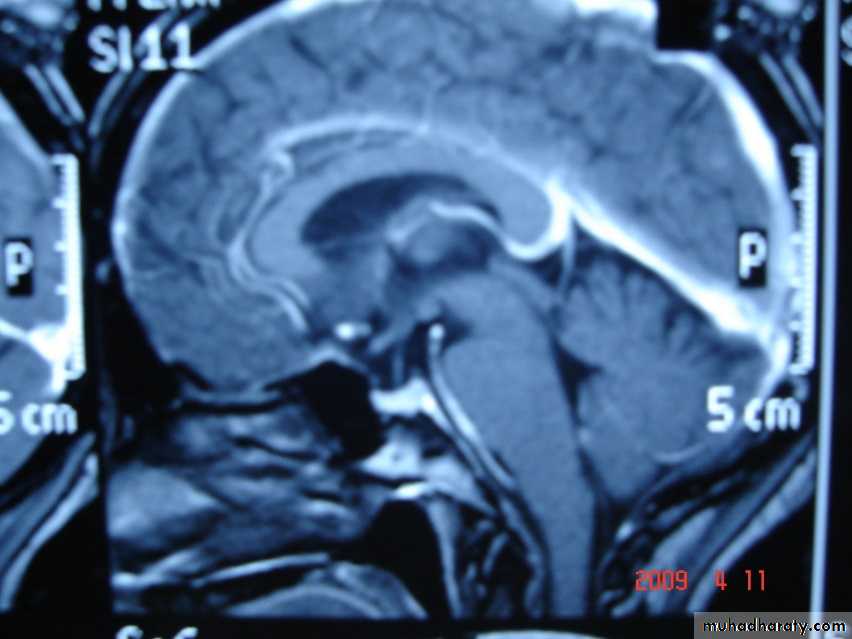

Sagital section of brain ( T1 w post contrast injection)

ARNOLD CHIARI MALFORMATION

1-Donward herniation of cerebellar tonsil & medulla oblongata beneath level of foramen magnum.

2- elongation of 4th ventricle.

3- associated with aqueduct stenosis.

4- associated with myelomeningocele.